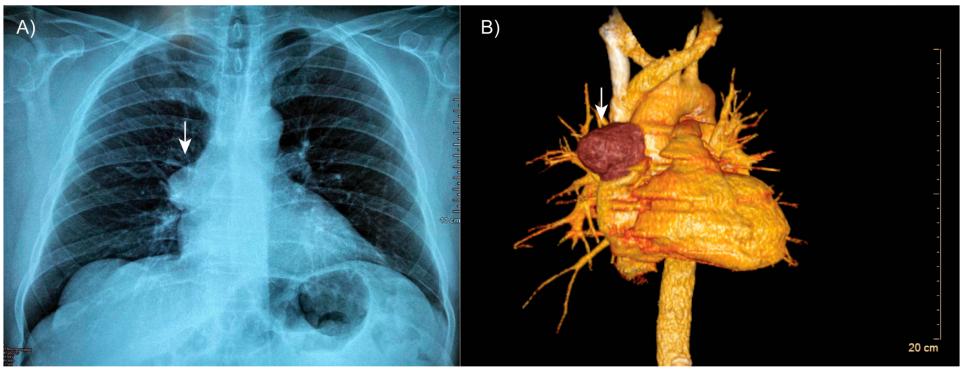

胸部计算机断层扫描显示肺野扩张良好,无实变迹象(图1A)。然而,在右前上纵隔观察到一个明确界定的包膜结节性阴影(图1B)。值得注意的是,肿瘤非常靠近邻近的血管结构,但没有证据表明有侵袭。

图1 患者的断层扫描。(A)胸部计算机断层扫描显示右前上纵隔内有一个明确的包膜肿块(箭头)。(B)三维重建显示病变(箭头)非常靠近邻近的血管结构,没有侵入的证据